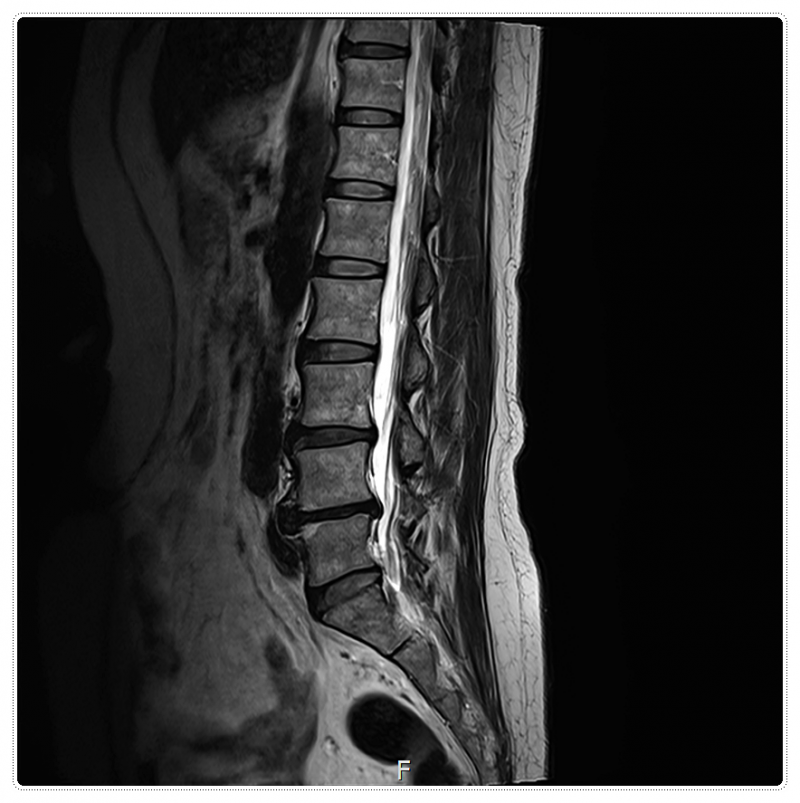

우리 척추 사이에는 푹신한 쿠션 같은 디스크가 있는데요.

이게 뒤로 밀려 나오면서 다리로 가는 신거 전달 길목인 신경을 꾹 누르게 됩니다.

이것이 바로 많은 분들이 고생하시는 방사통의 시작이죠.

특히 요추 3번, 4번, 5번 부위는 우리 몸의 하중을 가장 많이 견디는 곳이라 압력이 쏠리기 쉽습니다.

이 과정에서 요추 3, 4, 5번 디스크는 원래 견뎌야 할 무게보다 훨씬 무거운 압력을 받게 되죠.

뼈와 뼈 사이의 간격을 미세하게 벌려주어 눌려 있던 디스크가 숨을 쉴 수 있는 '공간'을 확보해 주는 것이죠.